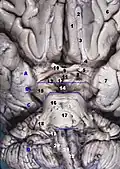

Корональный срез головного мозга через промежуточную массу третьего желудочка

Основание мозга